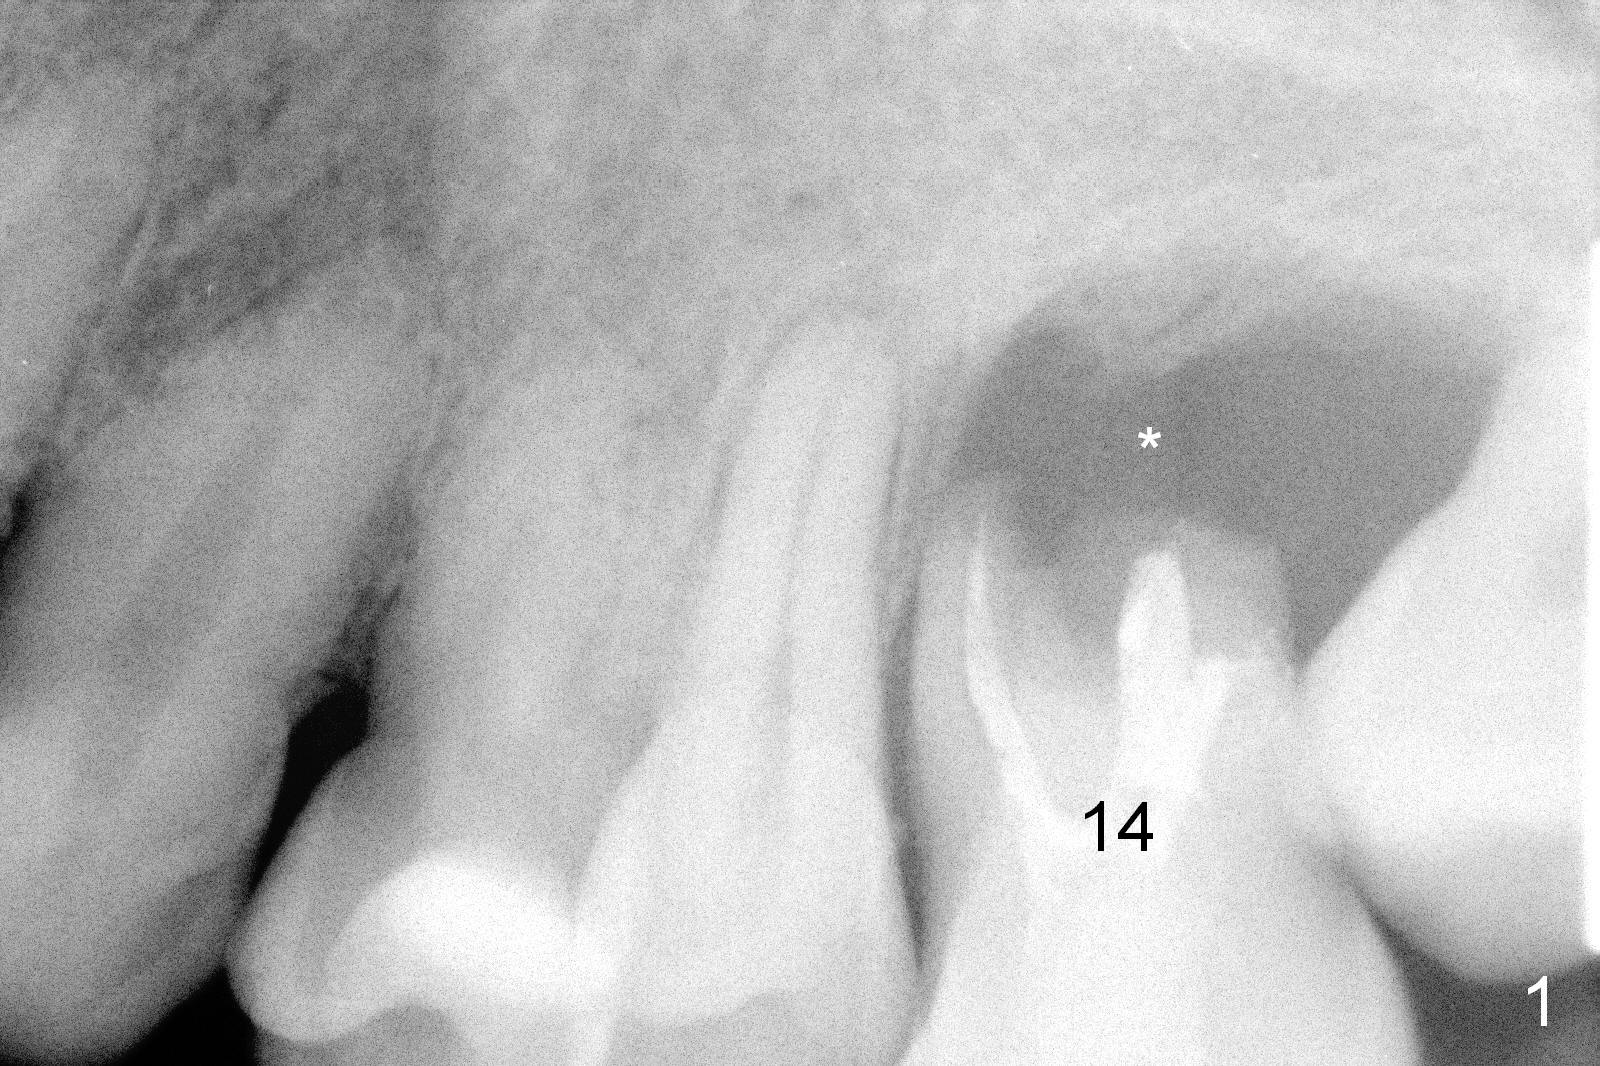

A 42-year-old man (XK) has perio-endo disease at the tooth #14.  After root canal therapy (Fig.1), the tooth remains nonsalvageable.  The bone loss is extensive (Fig.1 *) and uneven (more bone mesially than distally) after extraction (2% Xylocaine/1:50,000 Epinephrine).  A bone-level implant is placed in an ideal depth (Fig.3 UF; Fig.4 SM), irrelevant of the gingival margin, first.   Place bone graft distally (Fig.3 red circles) before choosing a proper abutment.  For example, there is plenty of combination to choose cuff and abutment lengths for a SM or UF implant (Fig.4).